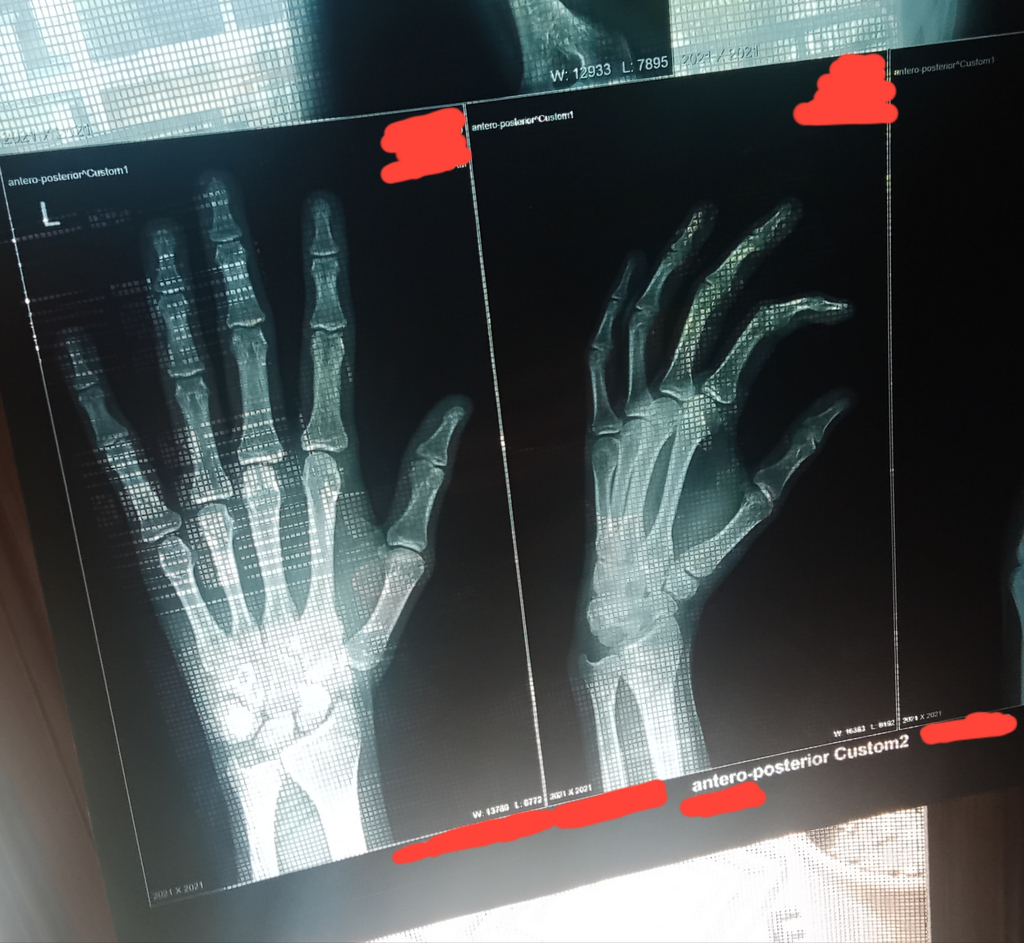

how tall?i got mine like 3 weeks ago and they were closed, i dont think i ever cried that hard in my life(mark me as solution)

176cmhow tall?